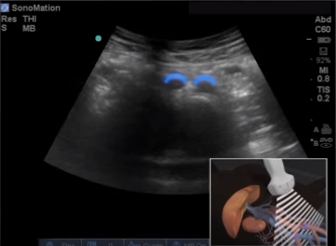

Transversale Schnittebene